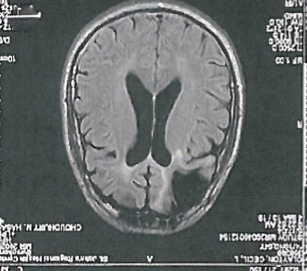

The scan of Cecil Clayton’s brain succinctly tells the story. In the front left corner of his skull, where his frontal lobe would normally be found, there is a gaping black hole about the size of a fist.

clayton brain scan

The scan of Clayton’s brain. Photograph: Supplied

The evidence of Clayton’s mental impairments – and hence his constitutional right to protection – is considerable, dating back many years. In addition to that image of his brain scan, psychological evaluations stretching back to 1978 have chronicled the after-effects of his severe brain trauma.